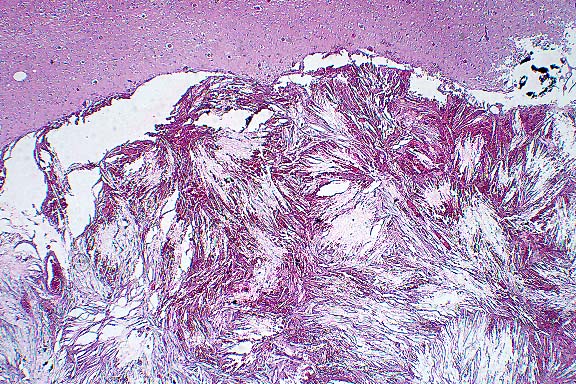

Case 3: Cerebrum. Multiple variably sized nodules expand the meninges and compress adjacent brain substance. These nodules contain free RBCs, macrophages, and abundant acicular clefts (cholesterol clefts). (2x obj).

All three meningeal masses have similar histology, composed of well- circumscribed proliferations of elongated spindle cells with fine cytoplasmic extensions and fibrillary processes, forming empty clefts with intervening hemorrhage. There is a slightly lobulated pattern with more plump spindle cells aggregated in a pseudolobular pattern. Little mineralization is detected but there are many accumulations of hemosiderin-laden macrophages. The masses consistently embed into and deform or atrophy the cortical gyri and, in one area, expand into a sulcus with focal infiltrations via Virchow-Robins spaces.